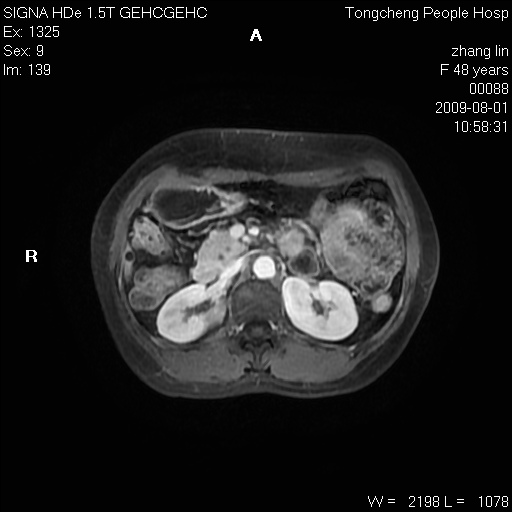

女,48岁。健康体检,彩超发现右肾占位性病变。平素健康。

临床诊断:右肾占位性病变,性质待定(囊肿?肿瘤?)。

上中腹部mr平扫+增强扫描,图像如下:

右肾上极见一类圆形病灶,t1wi呈等信号t2wi呈等高混杂信号,三期增强无强化,边界清---考虑囊肿出血。

同反相位均表现为等信号,病变无强化,考虑含蛋白的囊肿可能,弥散加权相或许有些帮助,

慢性胆囊炎